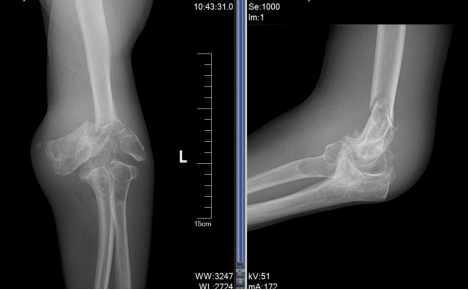

面对这一复杂的病例,贾丙申主任带领科室团队进行了周密的术前规划,精确掌握郭先生肘关节的畸形程度和骨骼形态。经过多次深入的术前讨论,最终制定了个性化的手术方案,精准预判了术中可能遇到的骨骼缺损、软组织平衡及神经血管保护等一系列难题。

术前X线。